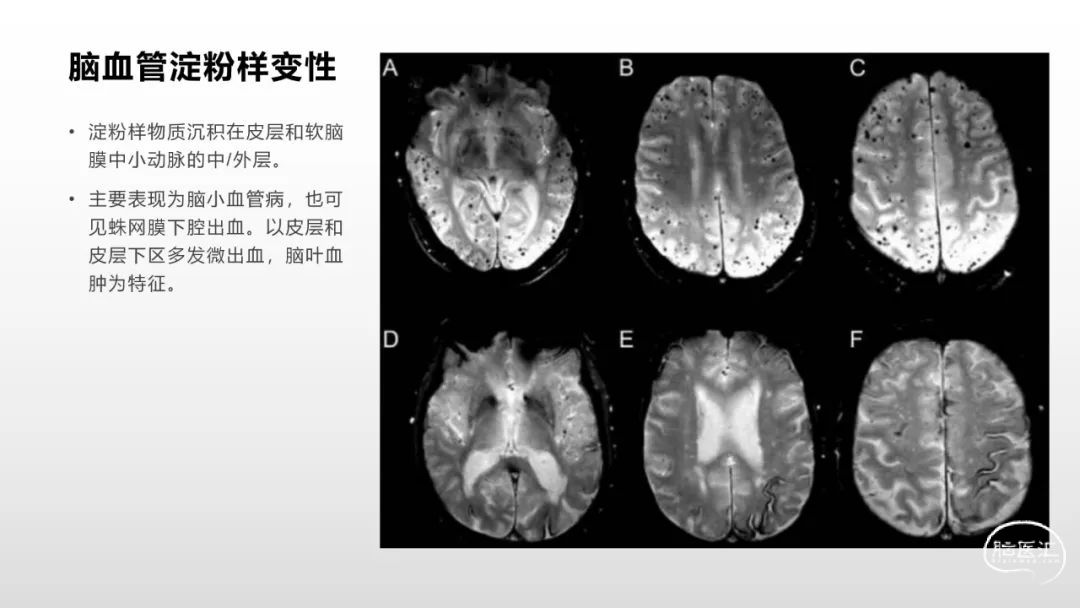

颅脑影像诊断基础知识讲座:《脑血管病》之出血、血管畸形、动脉炎及神经卡压